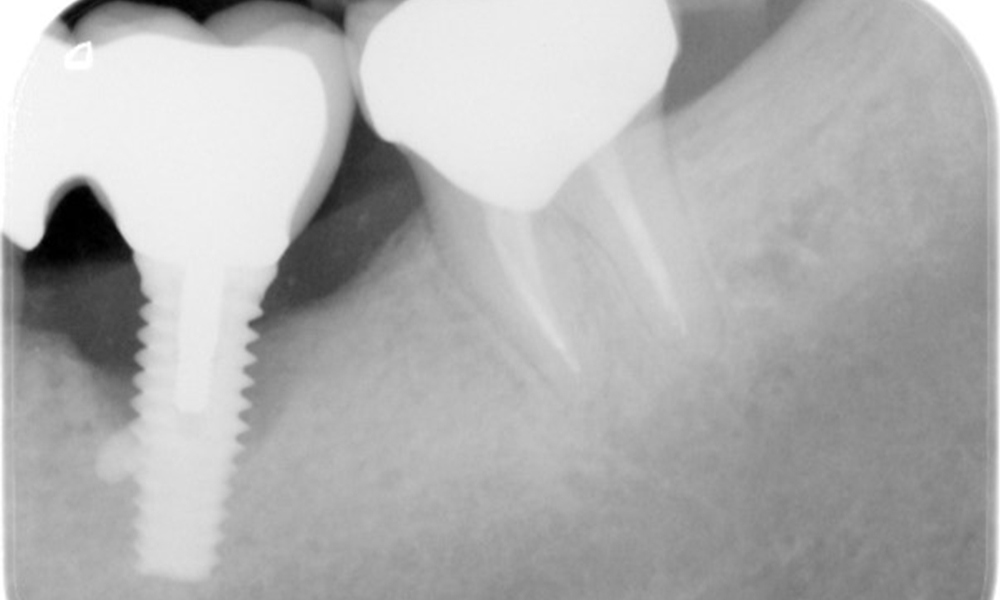

The patient has no particular risk factors with specific dental implications in his medical history. The key factor, therefore, is the requirement in terms of oral health. In this respect, there is evidence of a probing depth of 5 mm at the implant in the 3rd quadrant and, on the X-ray image, increased bone loss. The patient also has currently stable early periodontal disease and two active initial carious lesions.

The X-ray images show the progression of bone loss in the area of the implant in region 36: dental film from 11.02.2021 (left) and dental film from 18.01.2024 (right).